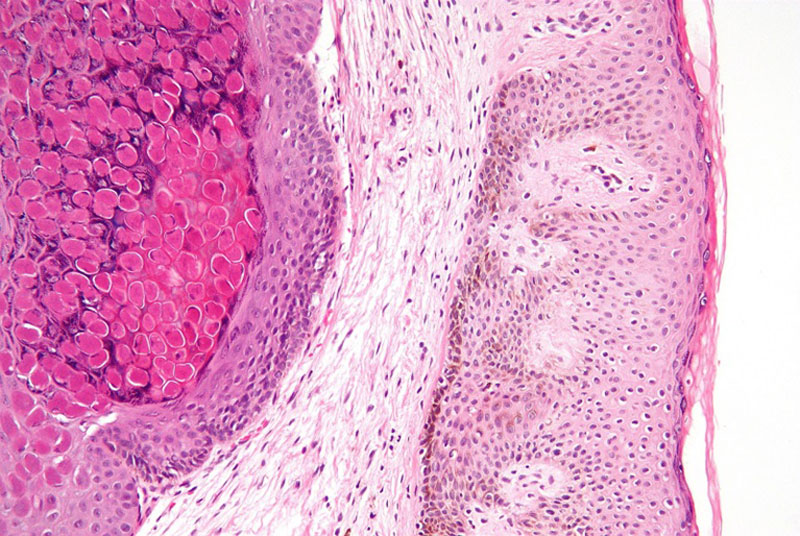

Về mặt mô bệnh học, nếu quan sát dưới kính hiển vi, hình ảnh u mềm lây thể hiện khá rõ nét là hình chiếc chén, với nhiều nhú biểu bì tập trung xung quanh lớp bì khiến chúng dày lên rõ nét. Phía bên trong là các thể Henderson-Paterson chứa virus gây bệnh từ quá trình nhân lên.

Hình ảnh u mềm lây quan sát dưới kính hiển vi